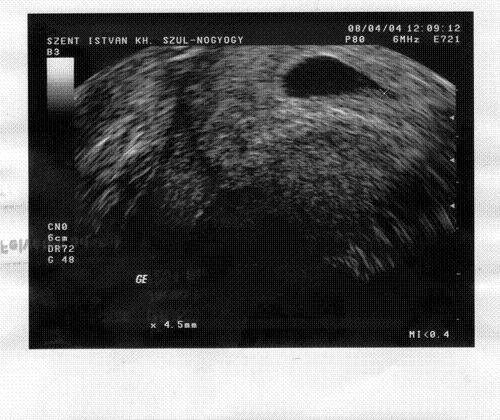

Kedden voltunk vérteszten. Nagyon kedvesek voltak. 29.-én lesz a 2. vérvétel és máj. elsejére ígérnek eredményt. Volt Szegeden sima vérvétel is. 6:45-8:15-ig vártam, mire behívtak, hiába volt időpontom 7-re. Vacak volt, szédelegtem. A vérképem hozzám képest jó, a vasam kevés 6.8 a referencia 8,8 és e felett.

A 12. heti UH-s eredményemre ráírták, h a korom miatt keressem fel a genetikust. Felhívtam, h megkérdezzem, a vérteszt ellenére is kell-e nála jelentkeznem. Finoman szólva elküldött a fenébe a vértesztemmel. Közölte, h az semmire sem jó, nem helyettesíti az aminot és irjam alá a védőnőnél, h vállalom a beteg babát. Közöltem, h EGÉSZSÉGESEK a gyerekeim és letettem. Szomorú, h ez a nő az egyetlen genetikus Szegeden. Szóval emiatt kérdem, h Veletek is aláriratnak ilyen papirt???????